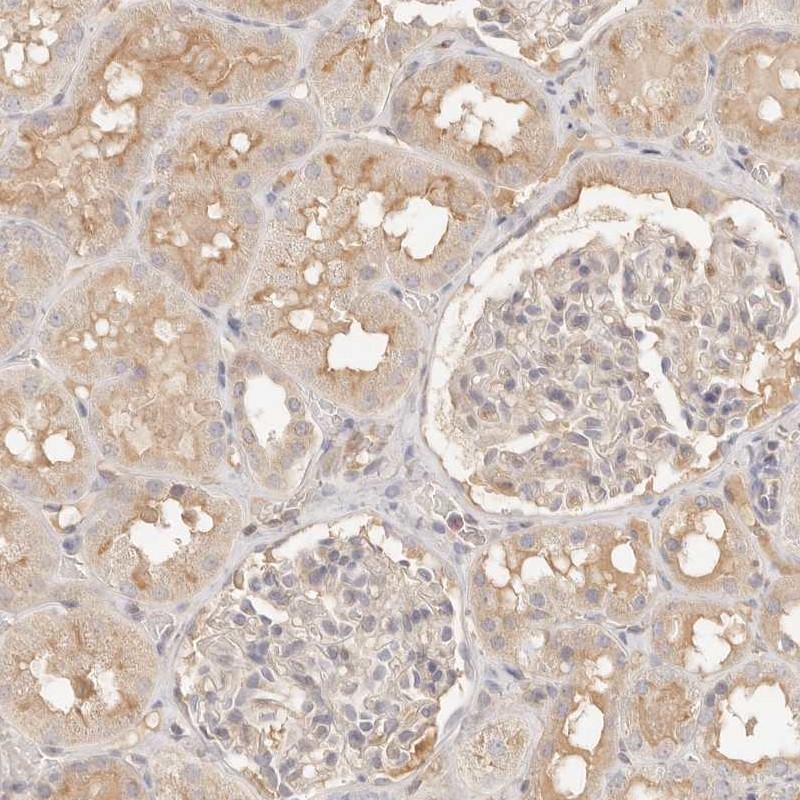

Immunohistochemical staining of human kidney shows moderate cytoplasmic positivity in cells in tubules.